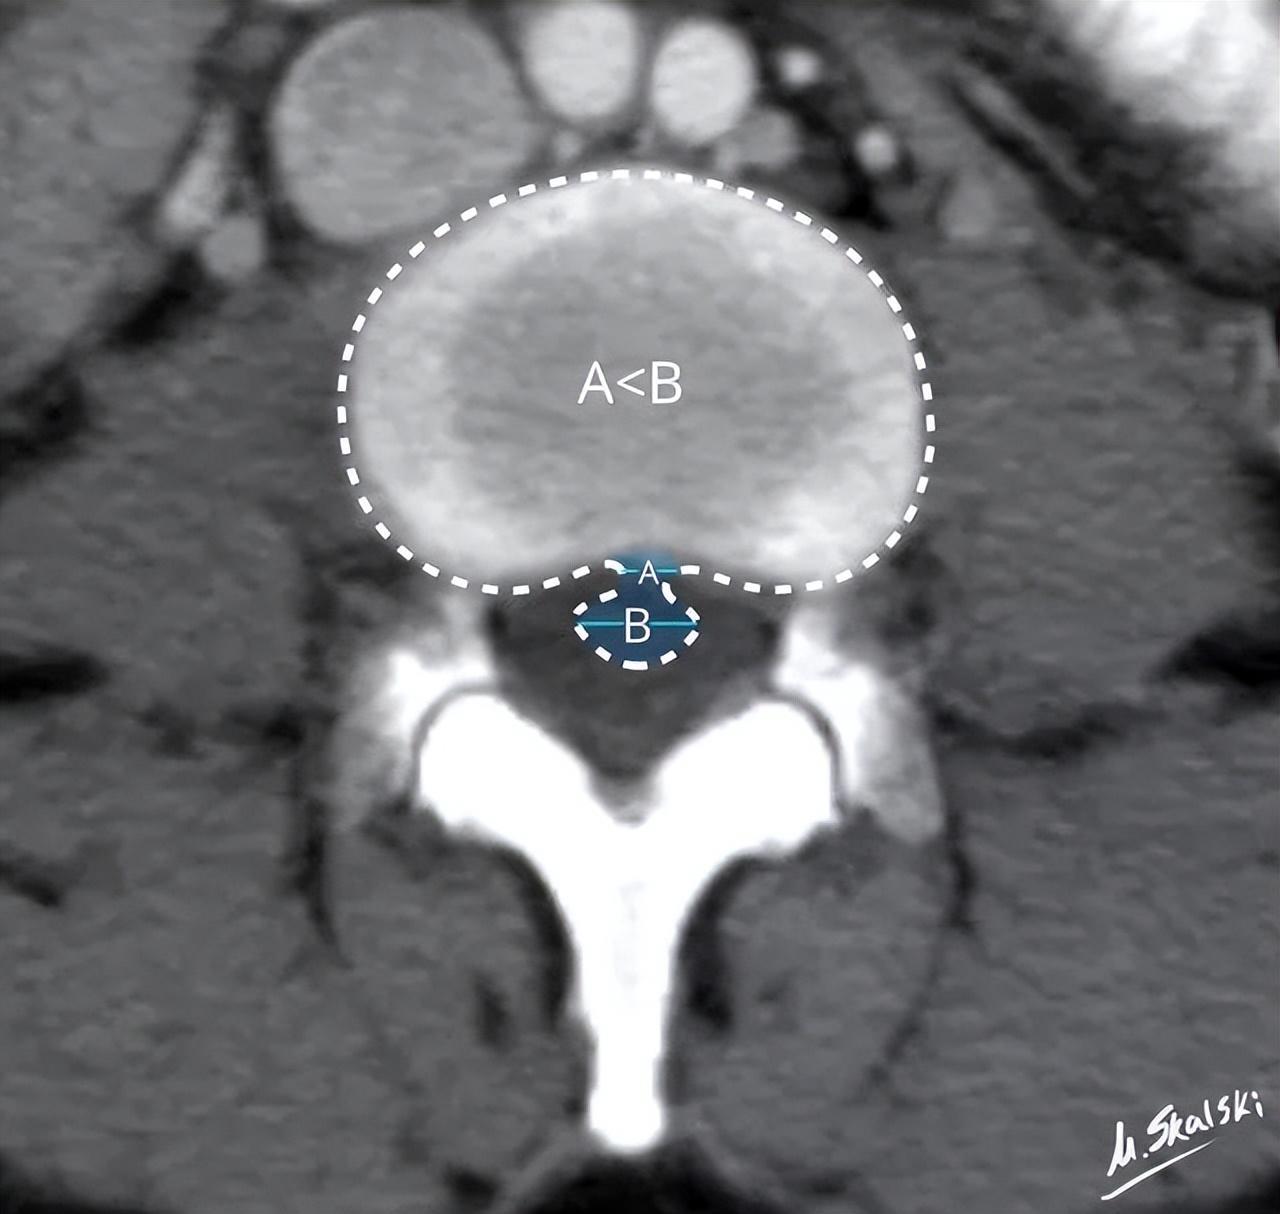

椎间盘突出的影像学定义为突出椎间盘的基底部(A)<突出组织的直径(B)